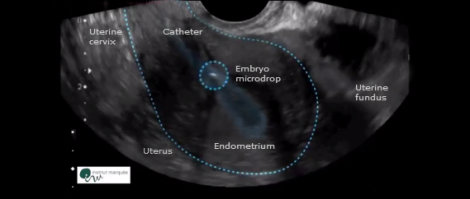

In the first images, we can observe how the microdrop with the embryos passes through the catheter and it is smoothly deposited 1, 2 or 3 cm away from the fundus of the uterus.

In the following ultrasounds the microdrop moves through the endometrial cavity with different undulating, vibratory, slow, fast movements and with resting stages.